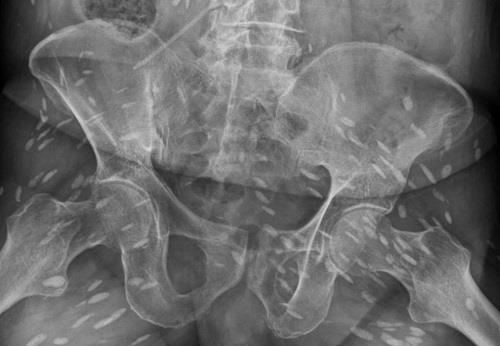

Hình ảnh chụp CT cho thấy có nhiều ổ sán nằm rải rác trong não bệnh nhân. Ảnh: Dân trí |

Qua thăm khám và chụp CT não, các bác sĩ phát hiện có 5 ổ sán nằm rải rác trong não ông S., trong đó có một ổ sán lớn trên đỉnh não của bệnh nhân gây phù não.